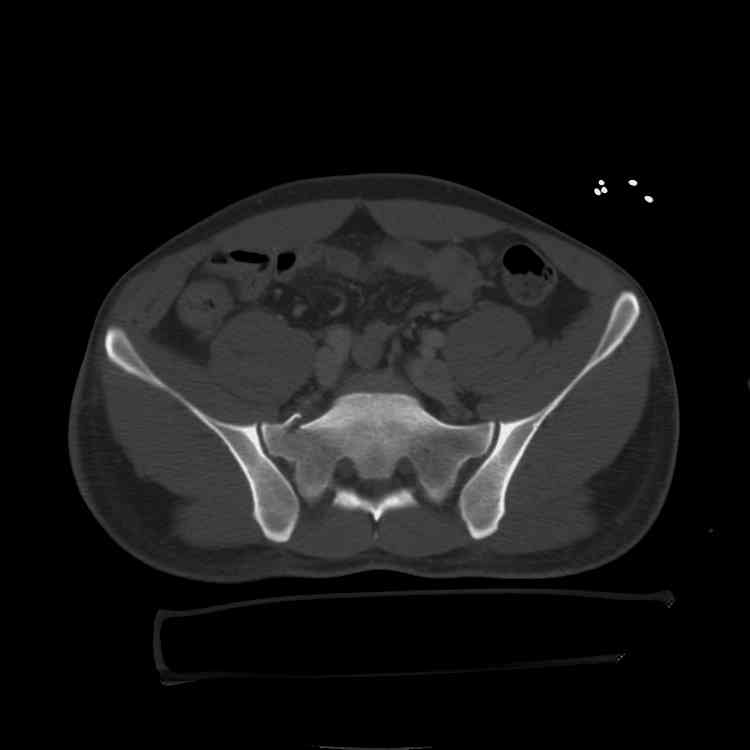

[Ortho] tilt fx

this is a healthy 22yo male. peds vs auto.

no other injuries. has anyone treated these non-operatively? thanks.